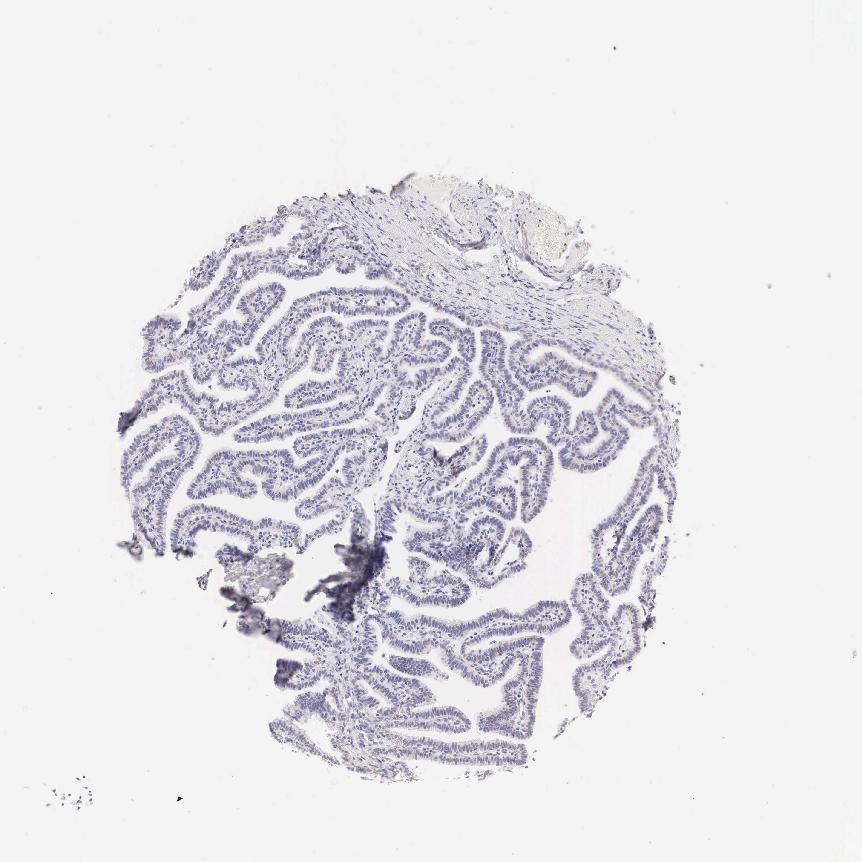

FALLOPIAN TUBE - Antibody stainingi

Antibody staining in the annotated cell types in the current human tissue is reported as not detected, low, medium, or high, based on conventional immunohistochemistry profiling in selected tissues. This score is based on the combination of the staining intensity and fraction of stained cells.

Each image is clickable and will lead to virtual microscopy that enables deeper exploration of all samples and also displays staining intensity scores, fraction scores and subcellular localization as well as patient and tissue information for each sample.

Antibody HPA001383Antibody CAB000043Antibody CAB020416Antibody CAB062555

Ciliated cells (cell body) --Not detected-

Ciliated cells (cilia axoneme) --Not detected-

Ciliated cells (ciliary rootlets) --Medium-

Ciliated cells (tip of cilia) --Not detected-

Glandular cells MediumNot detected-Low

Non-ciliated cells --Not detected-